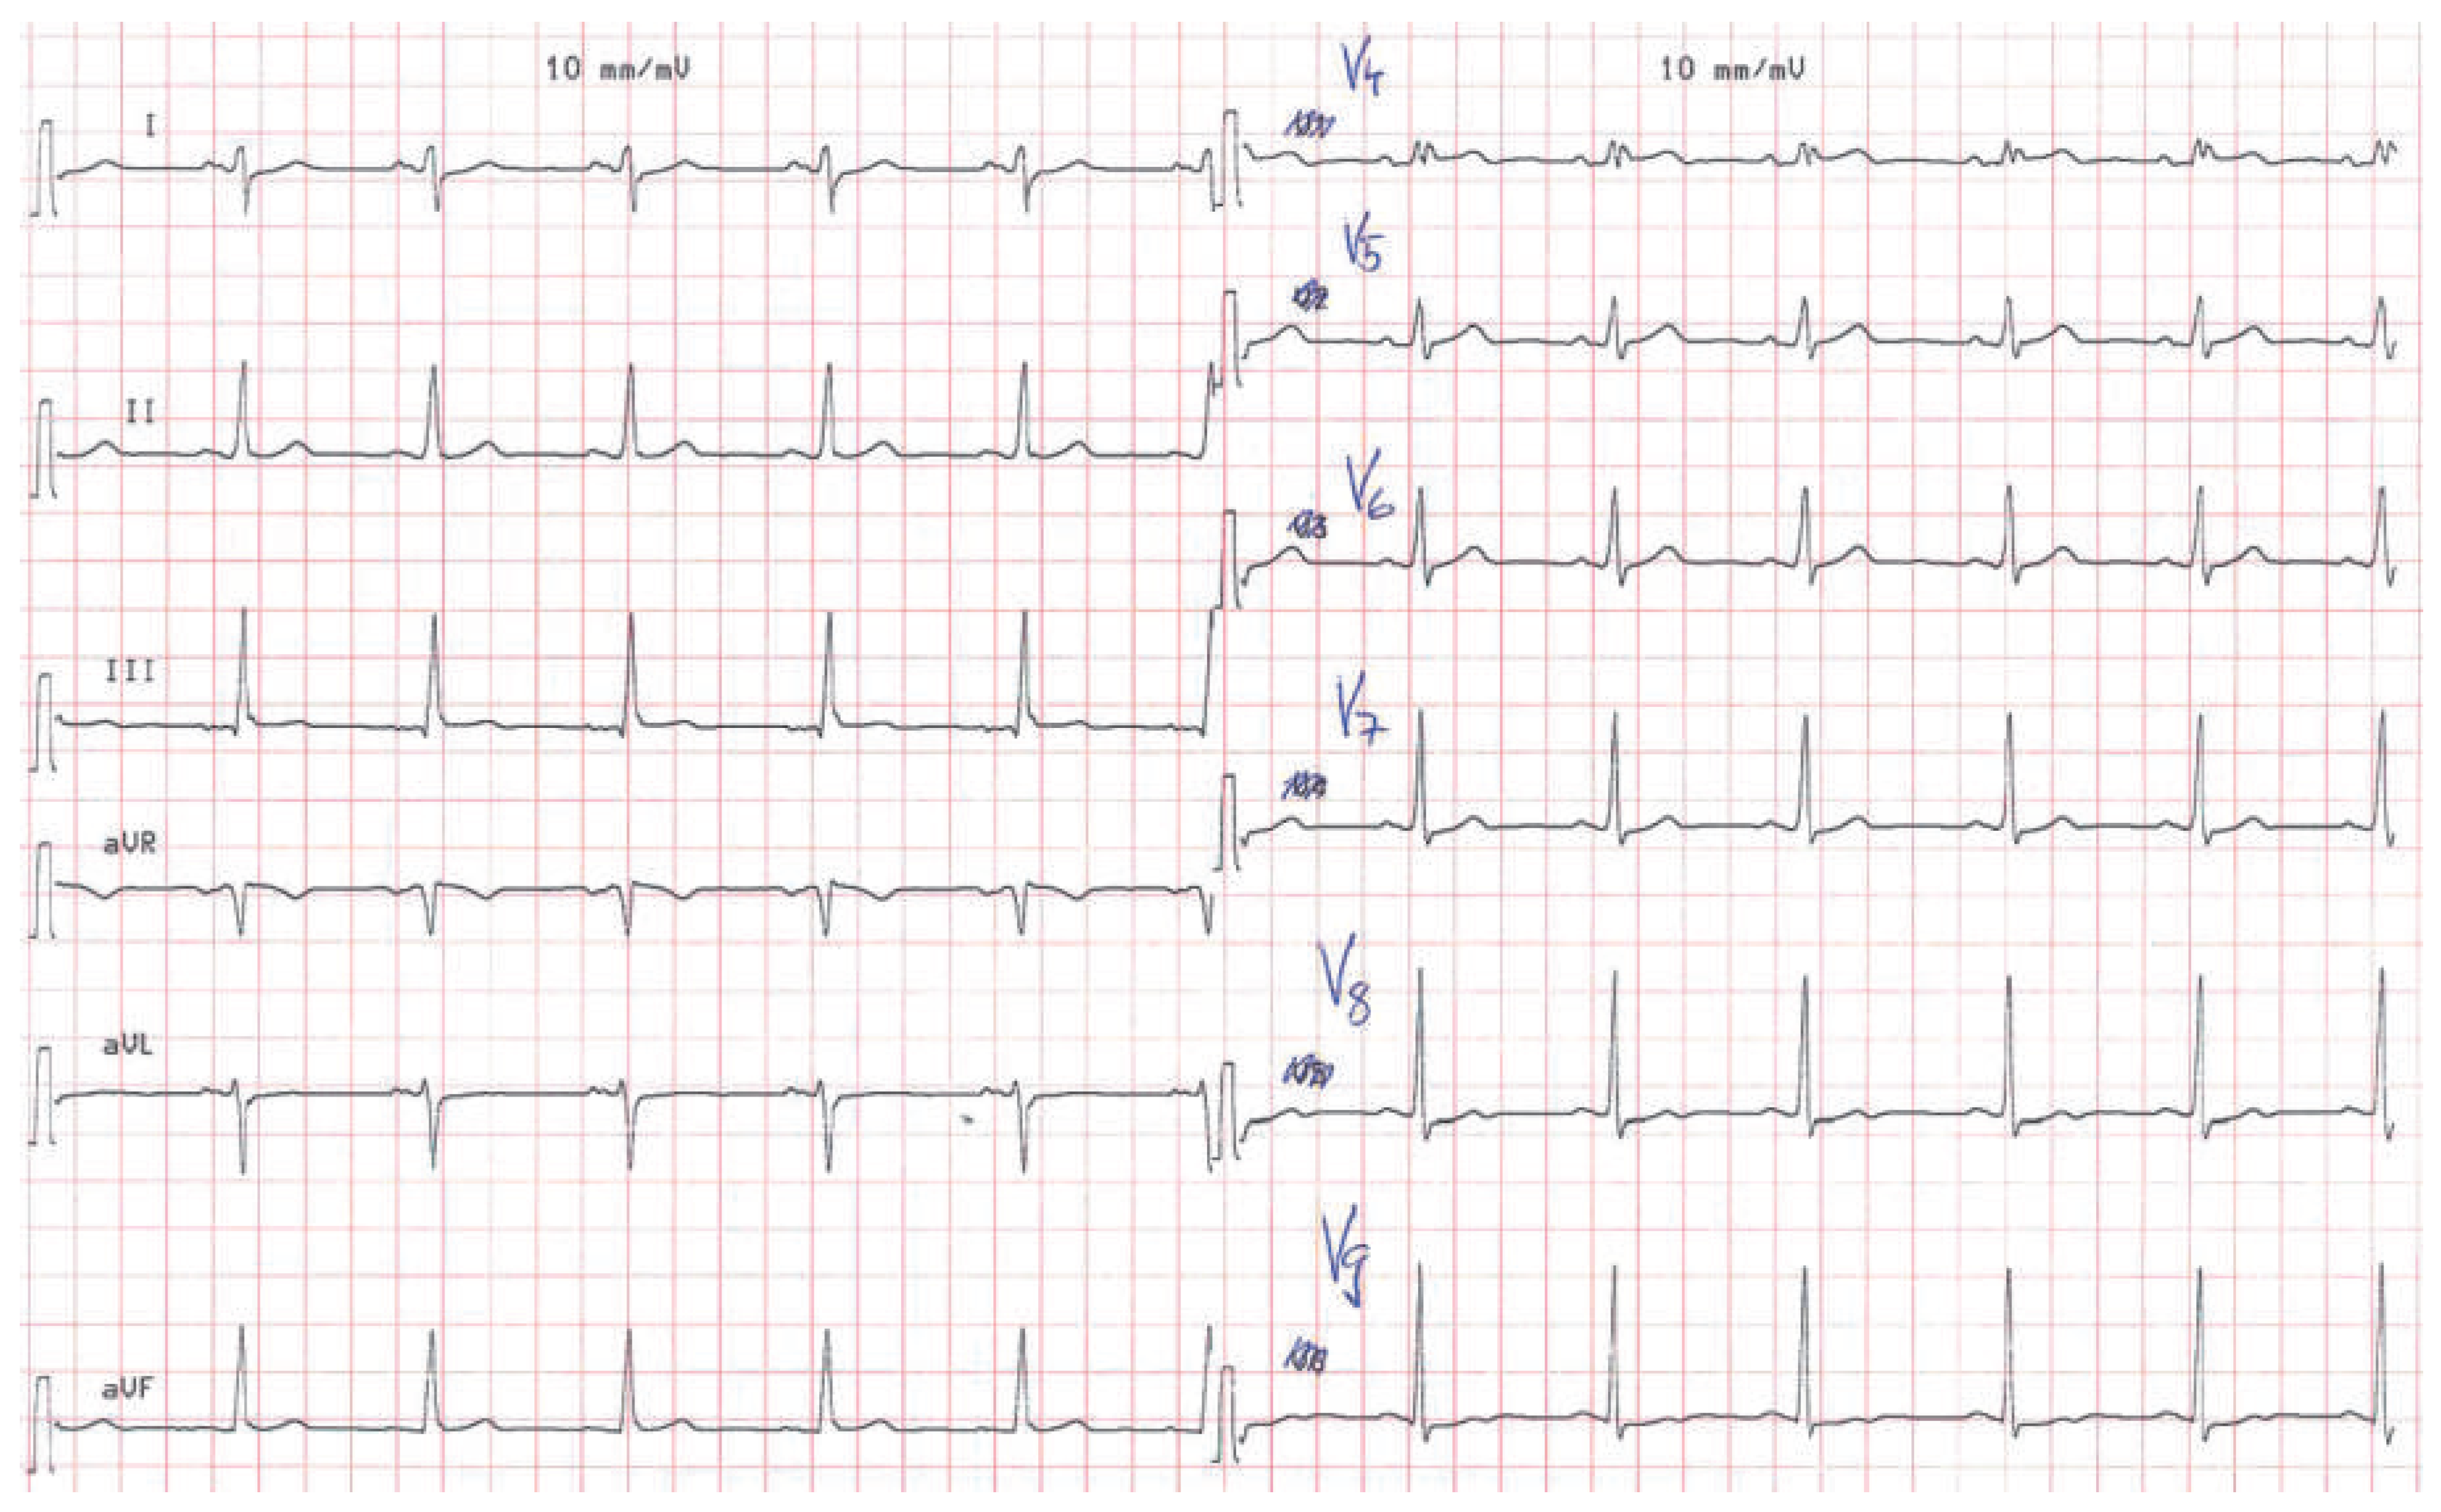

A 57-year-old male presented to the medical outpatient department with typical angina pectoris Canadian Cardiovascular Society (CCS) class II and dyspnoea on exertion during the previous weeks. Additionally he had retrosternal pain at rest and dyspnoea during the previous night. The patient had a a history of untreated arterial hypertension. On initial workup, the patient was in a stable cardiovascular condition with an office blood pressure of 150/88 mm Hg, and the cardiac examination was unremarkable. Blood tests revealed serially negative high-sensitivity troponins. Glycated haemoglobin was 6.4%, consistent with prediabetes, and lowdensity lipoprotein cholesterol was 2.5 mmol/l. An electrocardiogram (ECG) showed sinus rhythm, right axis deviation, signs of an incomplete right bundle-branch block with rR’ morphology in leads V1 to V4, and lateral displacement of the transition zone in the precordial leads, but no signs of acute ischaemia (Figure 1). On echocardiography, the image acquisition was difficult with a typical long axis view acquired in the fifth intercostal space in the midaxillary line (Figure 2) and apical views acquired from a posterolateral window (Figure 3). Computed tomography angiography (CTA) of the heart showed that the entire heart was displaced leftwards into the left hemithorax. Also evident was a lingula of lung tissue interposed between the aorta and the pulmonary artery indicating a congenitally absent pericardium (Figure 4). Additionally, the CT scan revealed coronary artery disease with soft plaques and >70% stenoses of the left anterior descending artery (LAD), the left circumflex artery (50%–70% stenosis) and the first marginal branch (>70% stenosis). Considering the diagnosis of a congenitally absent pericardium, the ECG was repeated, with leads V7–V9, showing a normal R-progression from V4 to V9 (Figure 5). Coronary angiography with primary stenting of a 95%–99% stenosis of the LAD artery and a 75%–95% stenosis of the first marginal branch resulted in complete resolution of symptoms.

Figure 1. Initial ECG showing right axis deviation, incomplete right bundle branch block and lateral displacement of the transition zone in the precordial leads.